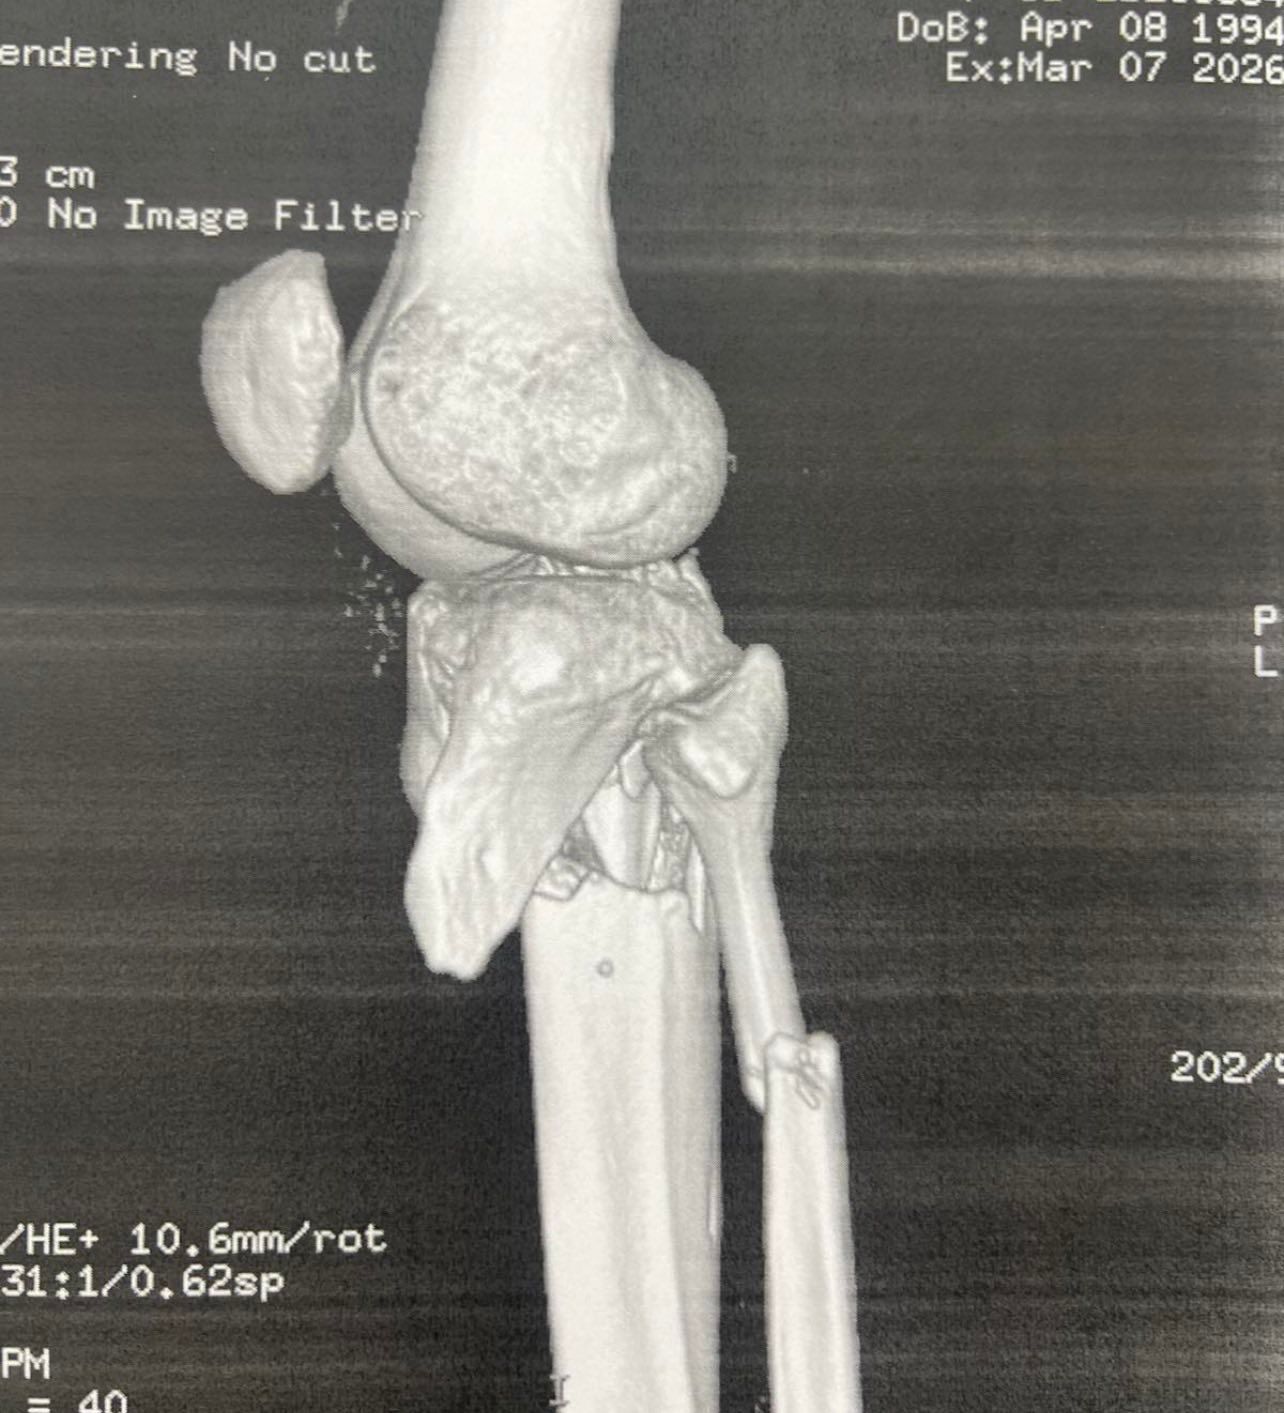

Πριν το χειρουργείο (απεικονίσεις τραυματισμού)

Τα κατάγματα του κνημιαίου πλατώ αφορούν την άνω επιφάνεια της κνήμης που συμμετέχει στην άρθρωση του γόνατος. Η ταξινόμηση Schatzker χρησιμοποιείται ευρέως για να περιγράψει το μοτίβο του κατάγματος.

Ο Schatzker τύπος VI είναι από τις πιο βαριές κακώσεις: πρόκειται για κάταγμα του πλατώ με μεταφυσιο-διαφυσιακή ασυνέχεια(δηλαδή «διαχωρισμό» της μεταφύσεως από τη διάφυση), συχνά μετά από υψηλής ενέργειας τραυματισμό. Τέτοιες κακώσεις μπορεί να συνοδεύονται από σημαντικό οίδημα/βλάβες μαλακών μορίων και απαιτούν ιδιαίτερη προσοχή στον χρόνο και στον τρόπο αποκατάστασης.